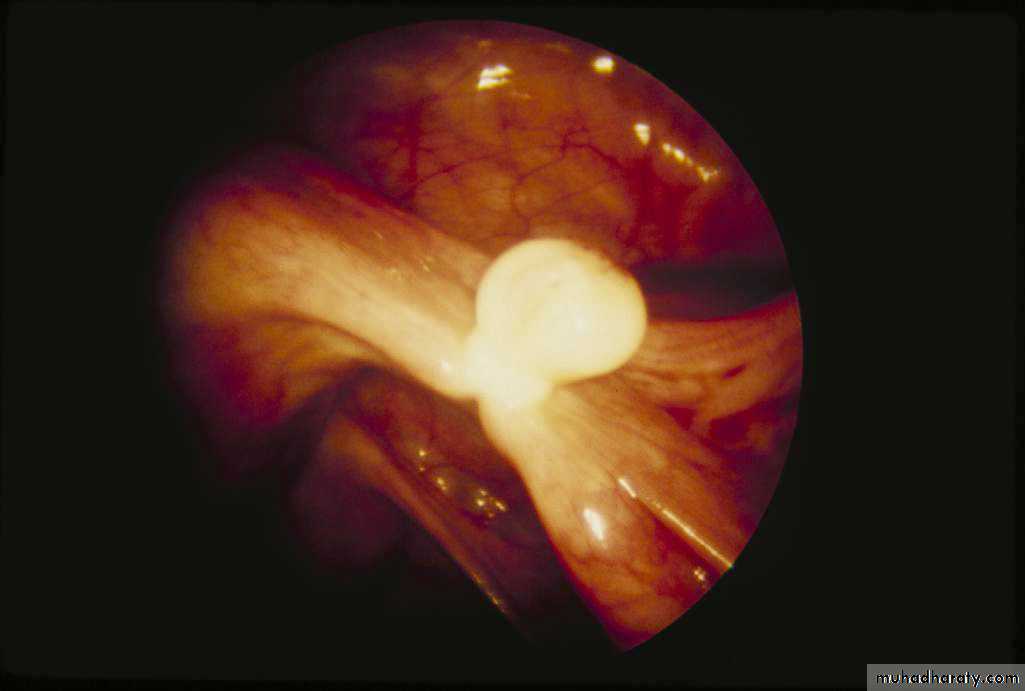

Falope ring

• Mechanical occlusion invented in 1974• Tubal occlusion accomplished by placing a silicone band around the tube

• Thicker tubes may be problematic

• May not be suited for postpartum

• Complications

• Increased patient discomfort during recovery – large area of necrosis

Failure Rate: 17.7/10001 (1.8%)

Falope Ring/Yoon Band